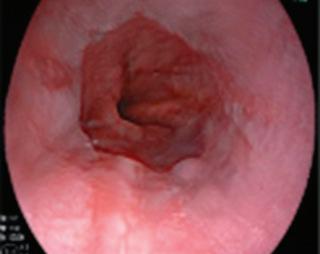

ЕНДОСКОПСКА РЕТРОГРАДНА ХОЛАНГИОПАНКРЕАТОГРАФИЯ Основна терапевтична стратегия при малигнена дистална билиарна

Фатери, дуоденална непроходимост или стеноза, затрудняваща маневреността на дуоденоскопа. Оказва се, че при малигнена дистална билиарна обструкция е налична туморна инфилтрация на дуоденума в 2545% от случаите[13].

Промените в зоната на на Папила Фатери, свързани с туморна инфилтрация, често налагат използване на напреднали техники на канюлация - „прекът“ сфинктеротомия, които от своя страна корелират с висок риск от усложнения като хеморагия, пост-ЕРХПГ панкреатит или перфорация на дуоденума или екстрахепаталните жлъчни пътища[14] Доказана е директната корелация между комплексността/сложност на процедурата и появата на усложнения. Честотата на постпроцедурен остър панкреатит варира значително